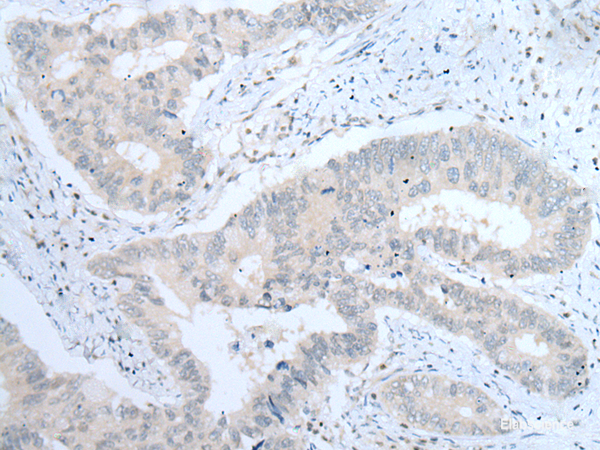

Integrins are heterodimeric transmembrane receptor proteins that mediate numerous cellular processes including cell adhesion, cytoskeletal rearrangement, and activation of cell signaling pathways. Integrins are composed of alpha and beta subunits. This gene encodes the alpha 8 subunit of the heterodimeric integrin alpha8beta1 protein. The encoded protein is a single-pass type 1 membrane protein that contains multiple FG-GAP repeats. This repeat is predicted to fold into a beta propeller structure. This gene regulates the recruitment of mesenchymal cells into epithelial structures, mediates cell-cell interactions, and regulates neurite outgrowth of sensory and motor neurons. The integrin alpha8beta1 protein thus plays an important role in wound-healing and organogenesis. Mutations in this gene have been associated with renal hypodysplasia/aplasia-1 (RHDA1) and with several animal models of chronic kidney disease. Alternate splicing results in multiple transcript variants encoding distinct isoforms. Protein function: Integrin alpha-8/beta-1 functions in the genesis of kidney and probably of other organs by regulating the recruitment of mesenchymal cells into epithelial structures. It recognizes the sequence R-G-D in a wide array of ligands including TNC, FN1, SPP1 TGFB1, TGFB3 and VTN. NPNT is probably its functional ligand in kidney genesis. Neuronal receptor for TNC it mediates cell-cell interactions and regulates neurite outgrowth of sensory and motor neurons. [The UniProt Consortium]